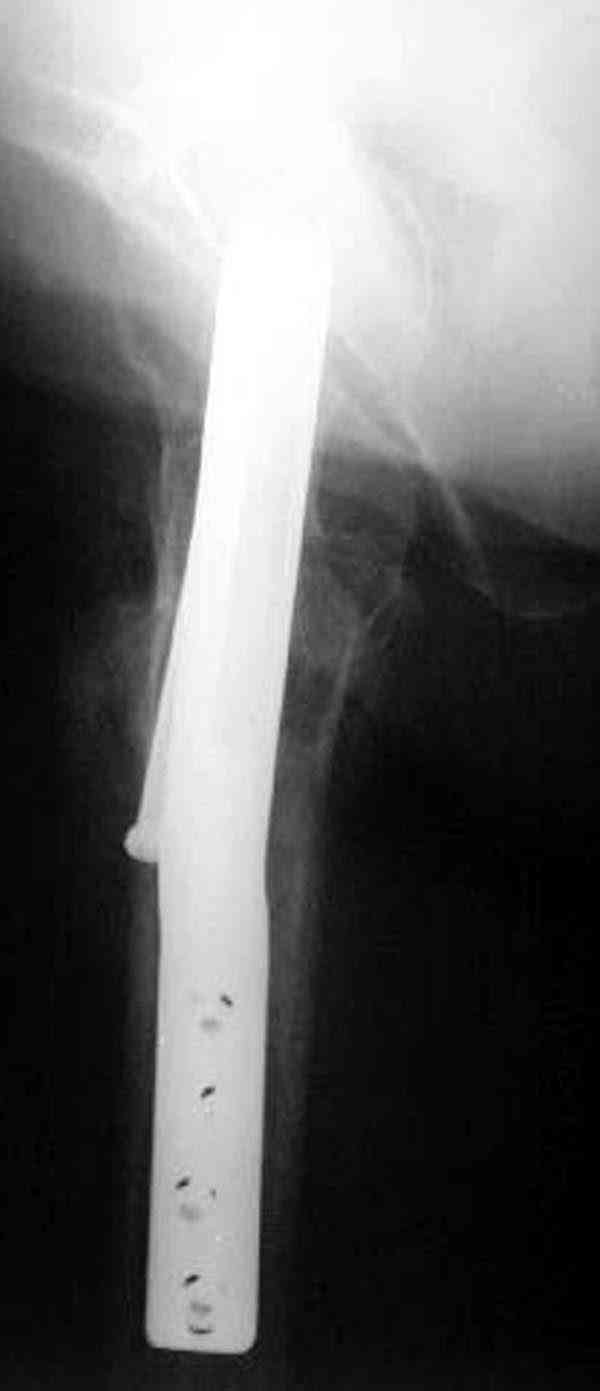

Здесь случай перелома из-за ослабления латерального кортекса через 3 недели после операции на шейке. Шурупы были установлены под большим углом, слабый латеральный кортекс не выдержал нагрузку.